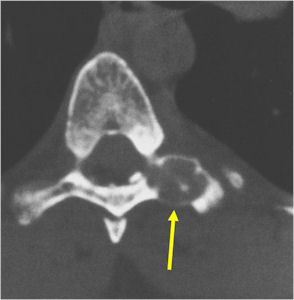

CT Scan:

- More useful for detecting mineralization and evaluating extent of bone destruction than plain X-ray

MRI:

- Also useful in determining extent

- There is often extensive edema around the tumor in the surrounding bone and soft tissues that can lead to a misdiagnosis of a malignant tumor.